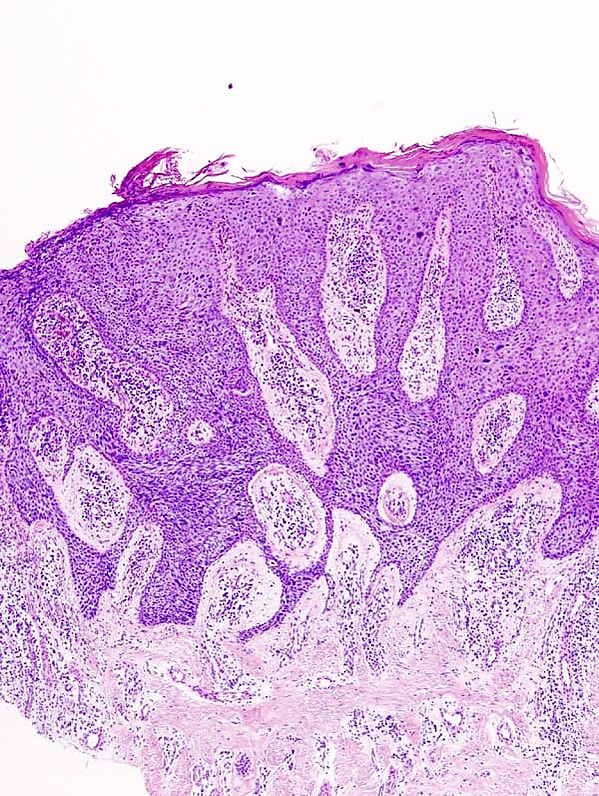

Гистологическая картина

Гистологически отмечаются гиперкератоз, паракератоз и акантоз с удлинением и утолщением эпидермальных выростов. Базальный слой чётко очерчен. В шиповатом слое выявляются акантотические разрастания, беспорядочно расположенные клетки с выраженной атипией, крупными гиперхромными ядрами и вакуолизацией. Присутствуют многоядерные гигантские клетки, атипичные митозы, очаговый дискератоз в виде «роговых жемчужин». Некоторые клетки напоминают клетки Педжета, но без межклеточных мостиков. При малигнизации формируются акантотические тяжи, проникающие в дерму с разрушением базальной мембраны и выраженным клеточным полиморфизмом[3].